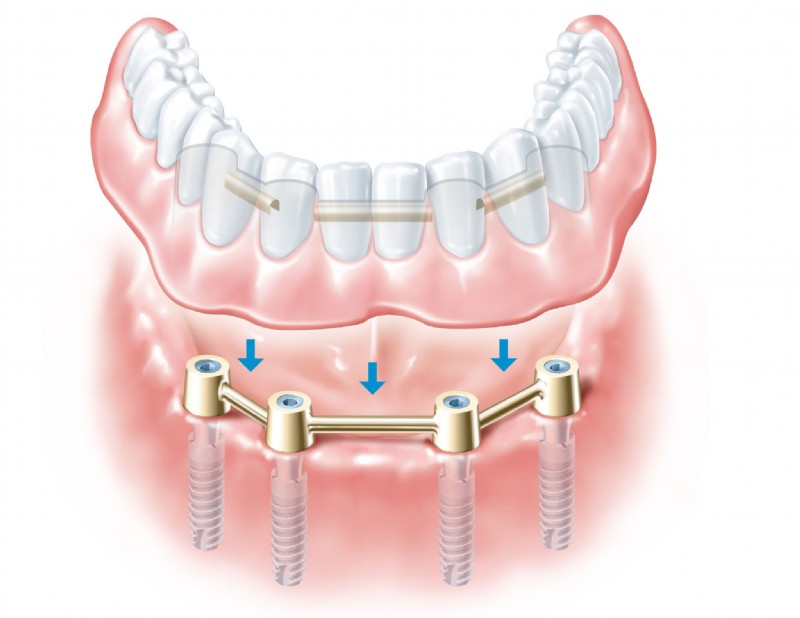

Als Spezialisten auf dem Gebiet der Implantologie wissen wir, wie man hochwertige Implantate stress- und schmerzfrei einsetzt und, wenn erforderlich, zuvor den Knochen aufbaut. Grundlegend werden in einem Beratungsgespräch all Ihre Fragen geklärt. Erst wenn Sie Vertrauen gefasst haben beginnen wir mit der professionellen Behandlung. Wir bieten Ihnen Einzelzahnimplantate, Brücken auf zwei oder mehreren Implantaten, zahnlose Kieferversorgung mit Implantaten, Brücken oder Halteelemente für Prothesen sowie maßgeschneiderte Lösungen für jedes individuelle Problem.

Hochqualitative künstliche Zahnwurzeln können natürliche Zähne sehr effektiv ersetzen. In einem ersten Schritt wird das Implantat-Bett aufbereitet, sodass das Implantat – eine Schraube aus Reintitan – problemlos in den Kiefer geschraubt werden kann. So können einzelne Zähne ersetzt oder Prothesen fixiert werden.